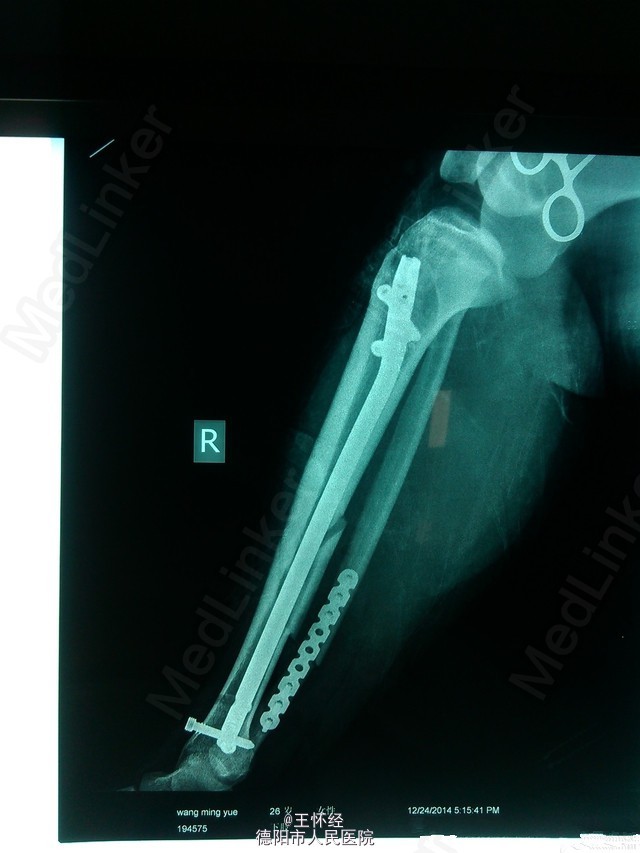

胫腓骨骨折闭合复位

患者女性,26岁,3日前滑雪致右胫腓骨粉碎性骨折,待时机适合时行手术治疗。